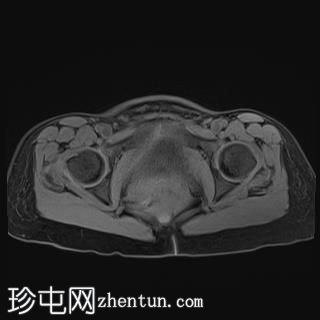

轴位

T1加权像

T1加权像平扫显示T1高信号,与CT上的高密度部分相对应,增强后无强化,符合血液成分表现。

影像表现提示附件扭转。患者被送入手术室行剖腹探查术。